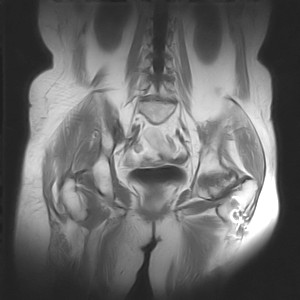

图像太差了 1、右侧臀肌旁脓肿? 建议增强 2、左侧股骨头坏死并半脱位

1、左侧股骨头坏死并髋关节半脱位;

2、右侧臀肌感染,(可能褥疮所致)